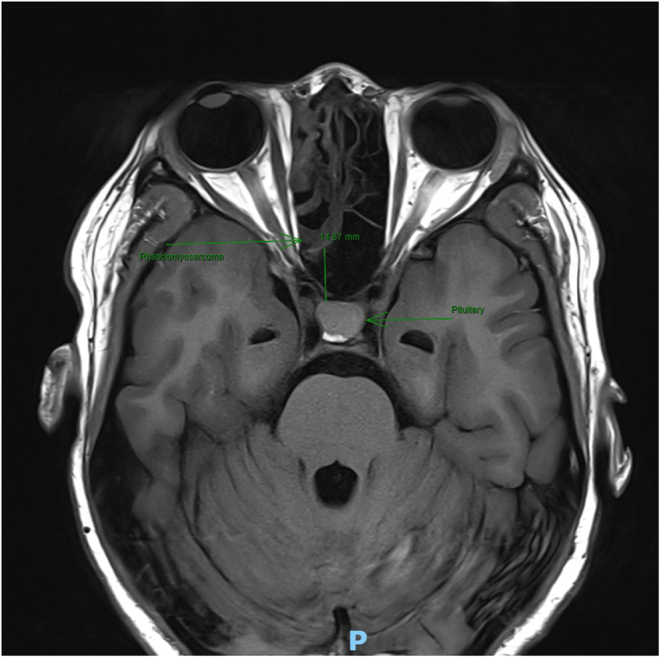

Summary: We describe and characterise the case of a 26-year-old female undergoing surgery for a right-sided sinonasal alveolar rhabdomyosarcoma who developed profound, transient arginine vasopressin deficiency (AVP-D, formerly central diabetes insipidus (DI)) associated with anaesthesia. In this case report, we characterise the development of AVP-D with serial copeptin and paired urine and serum osmolality measurements. Based on the anaesthetic agent's profile and the literature, we attribute this presentation to propofol exposure. We present a description of the literature on anaesthesia-associated DI as well as poignant learning points.